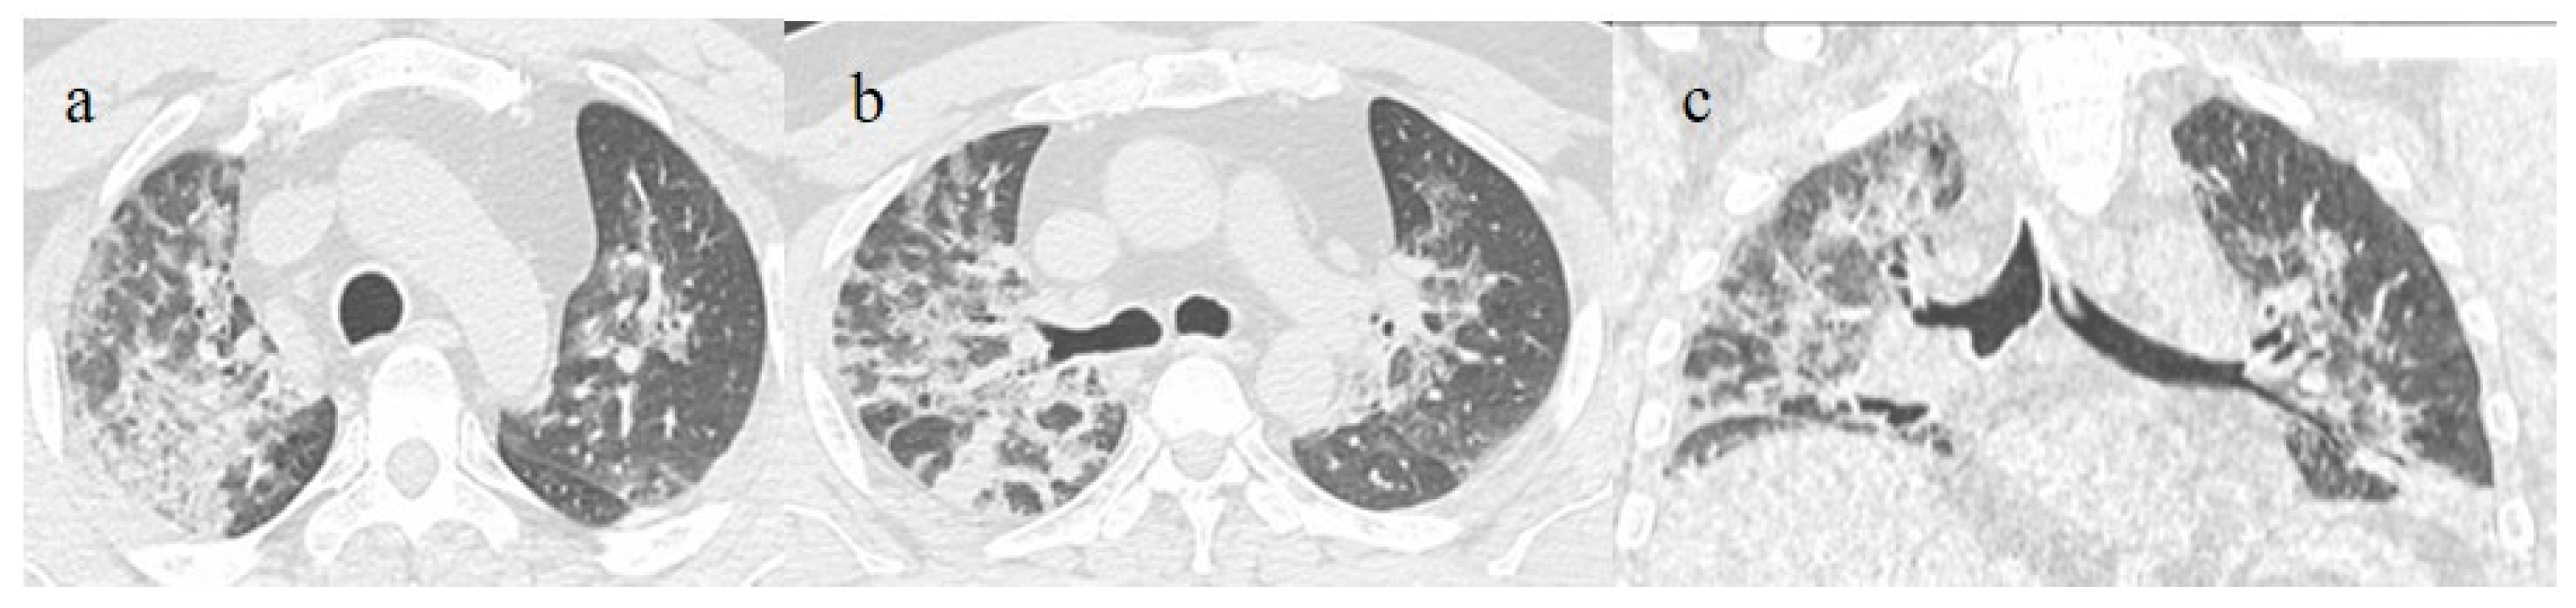

3.2. COVID-19 Pneumonia after Breakthrough Infections

- Brogna, B.; Bignardi, E.; Brogna, C.; Capasso, C.; Gagliardi, G.; Martino, A.; Musto, L.A. COVID-19 Pneumonia in Vaccinated Population: A Six Clinical and Radiological Case Series. Medicina 2021, 57, 891. [Google Scholar] [CrossRef]

- Wada, N.; Li, Y.; Hino, T.; Gagne, S.; Valtchinov, V.I.; Gay, E.; Nishino, M.; Madore, B.; Guttmann, C.R.; Bond, S.; et al. COVID-19 Vaccination reduced pneumonia severity. Eur. J. Radiol. Open 2022, 9, e100456. [Google Scholar] [CrossRef]

- Granata, V.; Fusco, R.; Villanacci, A.; Magliocchetti, S.; Urraro, F.; Tetaj, N.; Marchioni, L.; Albarello, F.; Campioni, P.; Cristofaro, M.; et al. Imaging Severity COVID-19 Assessment in Vaccinated and Unvaccinated Patients: Comparison of the Different Variants in a High Volume Italian Reference Center. J. Pers. Med. 2022, 12, 955. [Google Scholar] [CrossRef] [PubMed]

- Lee, J.E.; Hwang, M.; Kim, Y.-H.; Chung, M.J.; Sim, B.H.; Chae, K.J.; Yoo, J.Y.; Jeong, Y.J. Imaging and Clinical Features of COVID-19 Breakthrough Infections: A Multicenter Study. Radiology 2022, 303, 682–692. [Google Scholar] [CrossRef]

- Verma, A.; Kumar, I.; Singh, P.K.; Ansari, M.S.; Singh, H.A.; Sonkar, S.; Prakash, A.; Ojha, R.; Shukla, R.C. Initial comparative analysis of pulmonary involvement on HRCT between vaccinated and non-vaccinated subjects of COVID-19. Eur. Radiol. 2022, 32, 4275–4283. [Google Scholar] [CrossRef]